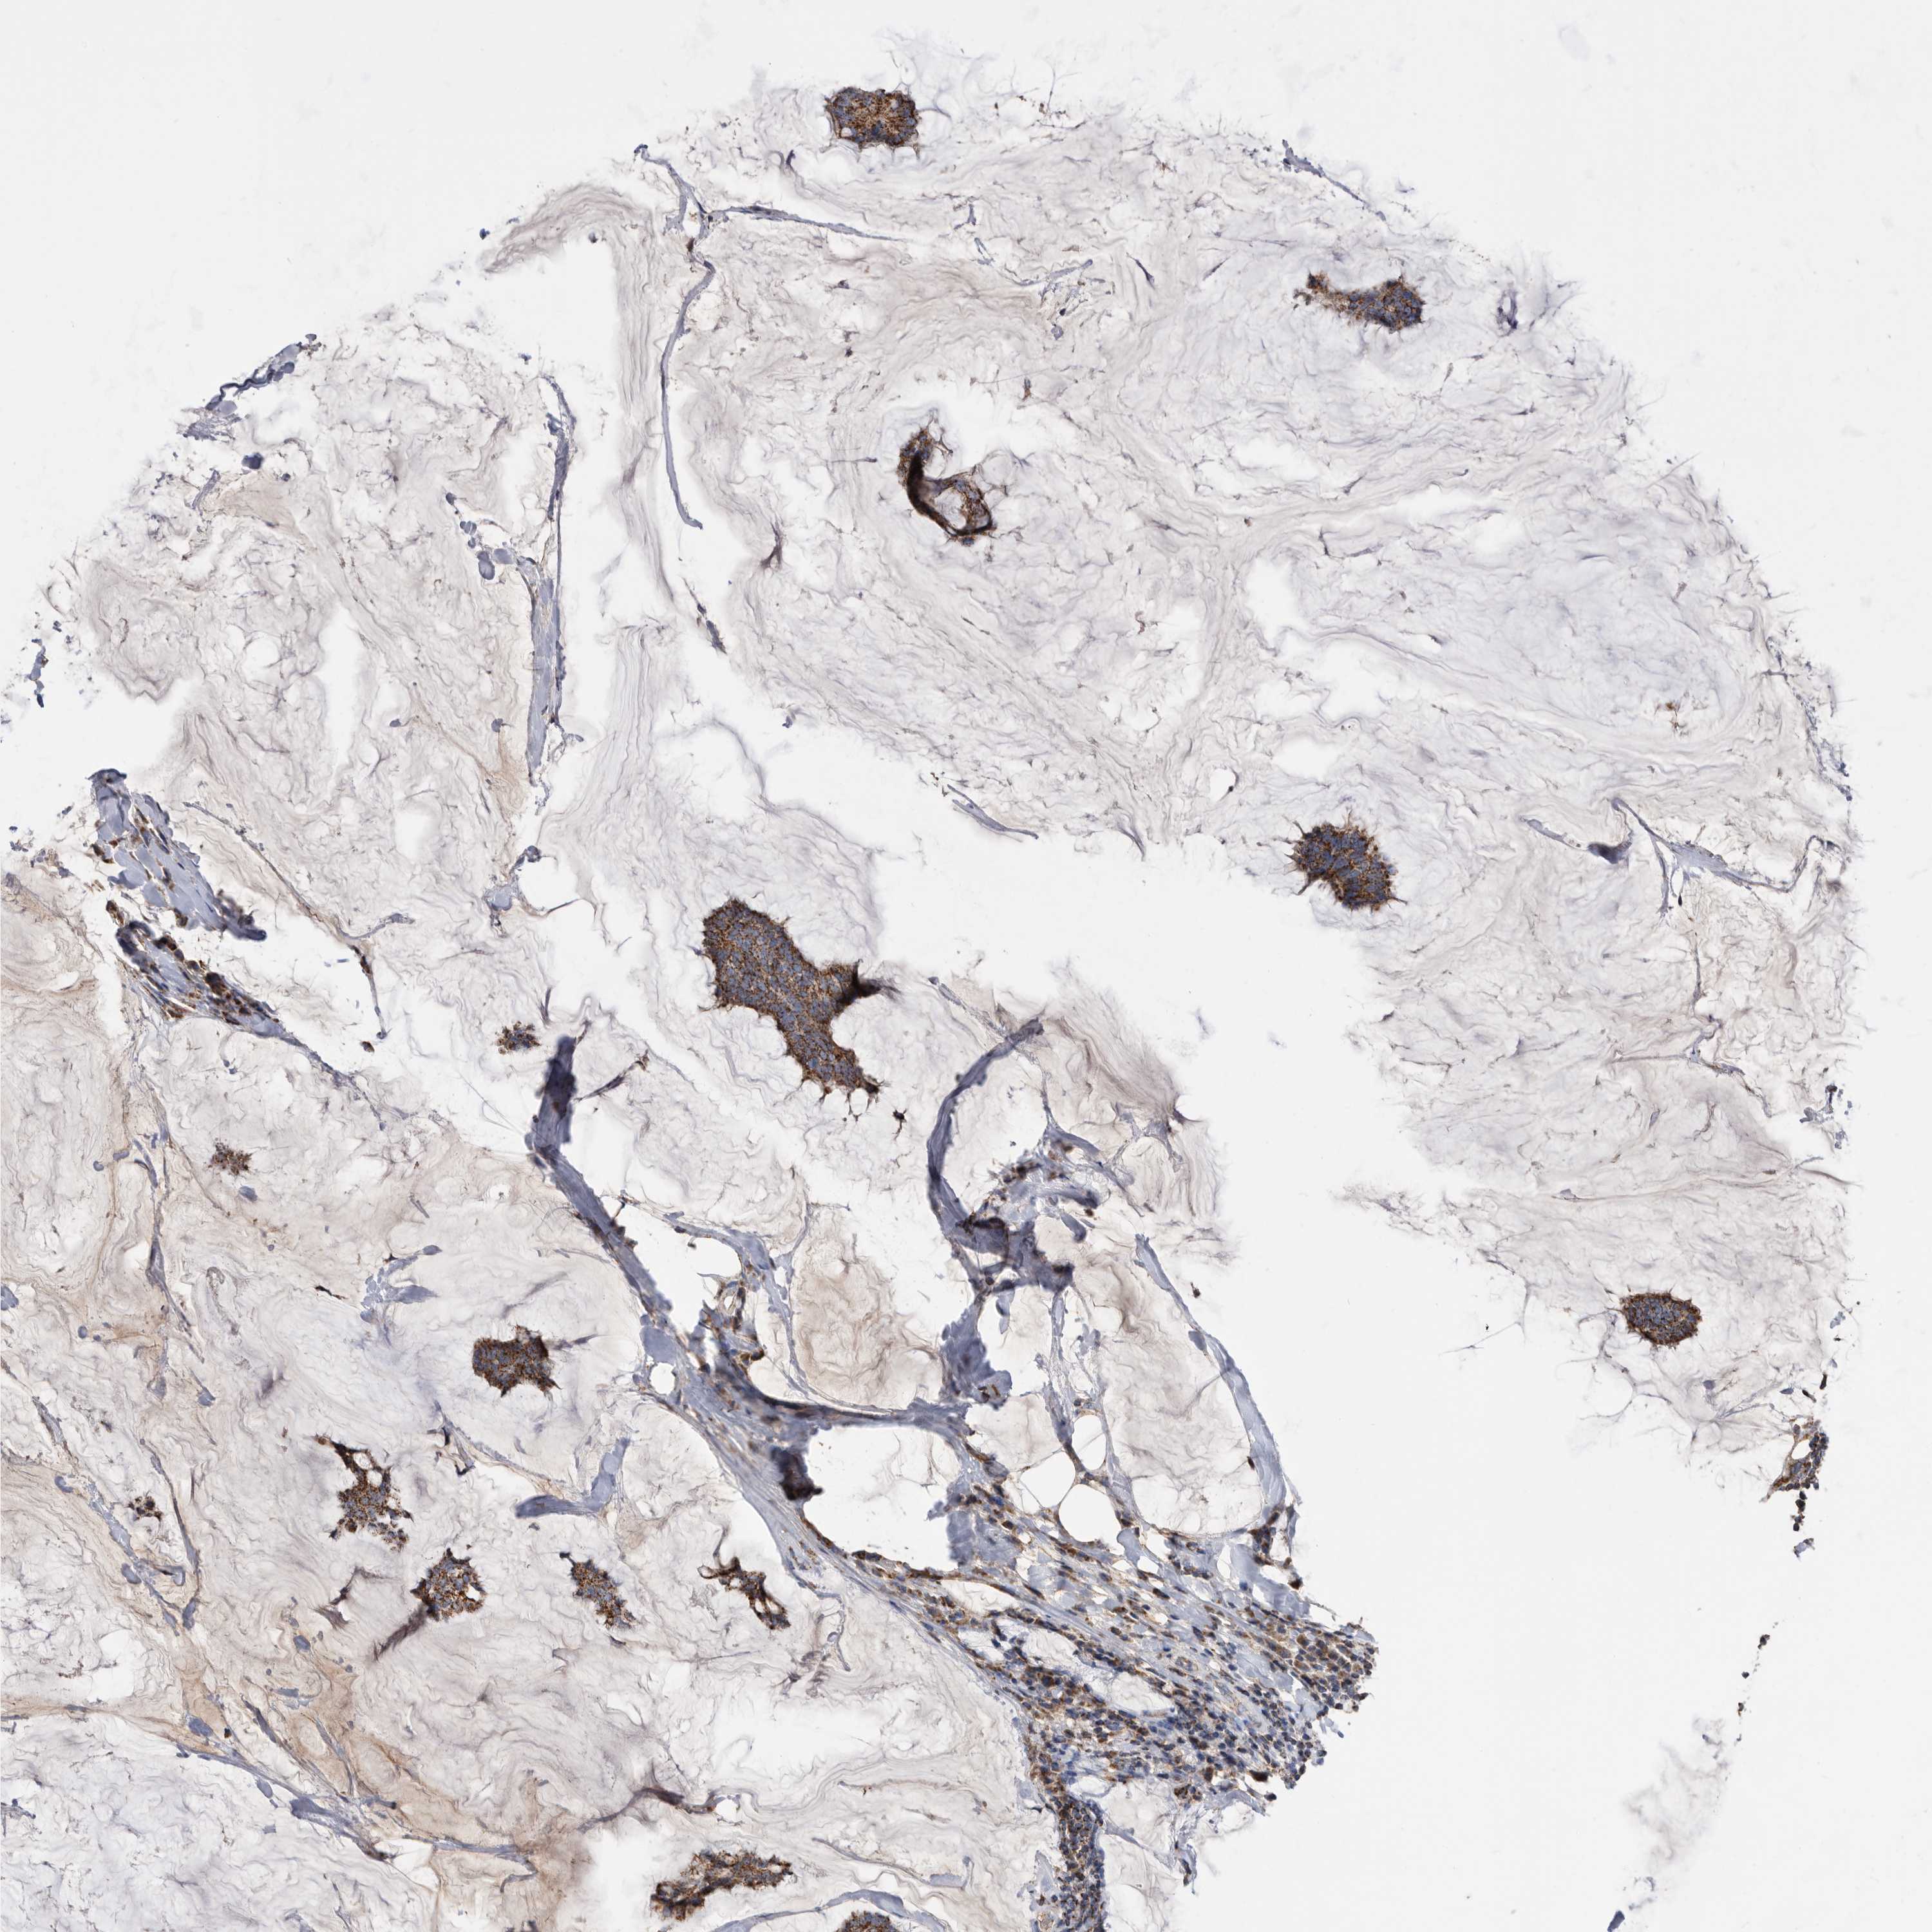

CANCER BREAST CANCER Show tissue menu

BRCA TCGA BRCA VALIDATION PROTEIN EXPRESSION